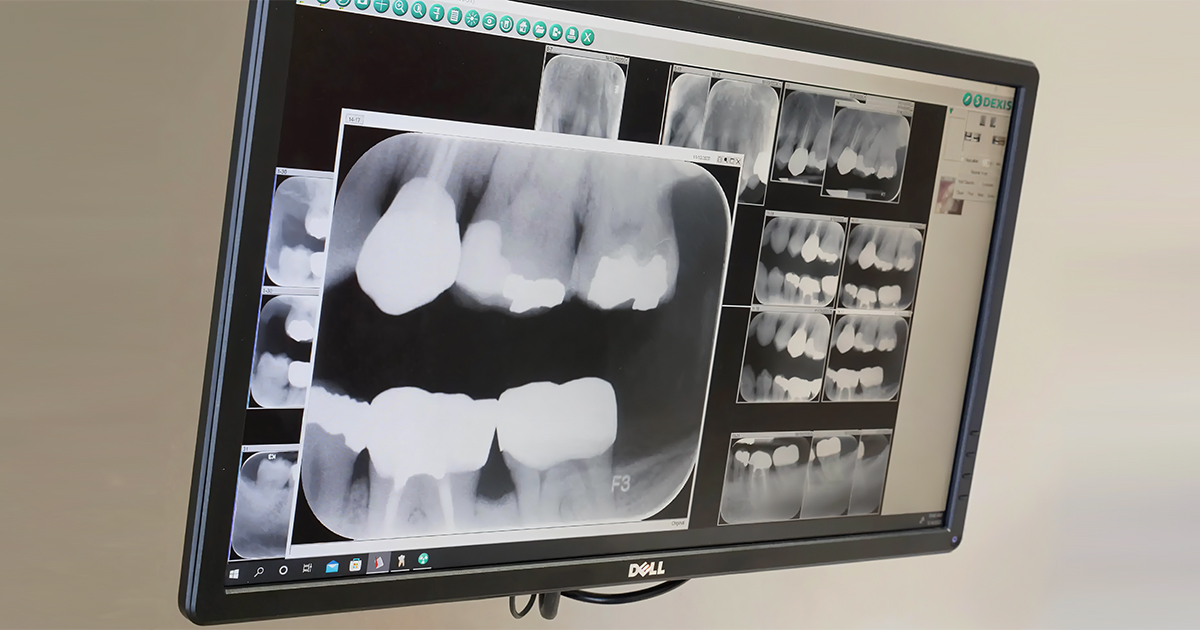

Digital radiography, commonly known as digital X-rays, is an advanced imaging technique used in dentistry that replaces traditional radiographic films with electronic sensing devices. It uses an X-ray machine to expose digital sensors or phosphor plates, creating images that are instantly displayed on a computer screen for immediate review. Beyond periapical or bitewing imaging, it also facilitates extraoral imaging such as OPG, cephalometric, and CBCT, which are essential in surgical planning, orthodontics, and implantology.

In contrast, digital radiography produces high-quality images with better contrast. These images can be zoomed in for further observation and easily adjusted for brightness and contrast using the software. This flexibility helps enable more accurate diagnoses and effective treatment planning.